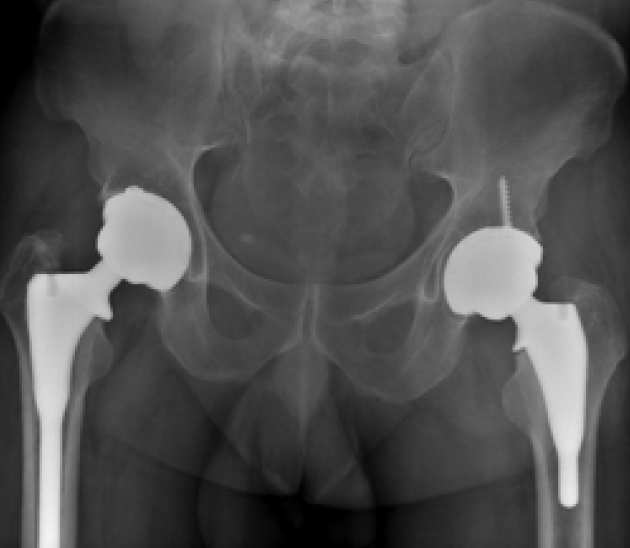

Total Hip Replacement (THR) is a highly effective procedure for relieving pain and restoring function. The JRI Furlong® HAC femoral stem is one such implant with good long-term survivorship. and published findings have shown a 97.4% survivorship at a mean of 17 years of follow-up in patients.

Our foremost intention is to assess the function and survival of the new Evolution® hip replacement implant. As part of ongoing developments in hip replacement implants, this new modification has been developed from an existing hip replacement stem, which has very good long-term results.